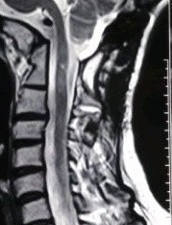

9月2日,我院神经外科在解放军昆明总医院封亚平教授的指导下,成功实施县内首台上颈椎、颅颈交接区手术,这标志着我院神经外科诊疗技术又迈上了一个新台阶。 40岁女性患者,因“头疼头晕伴左侧肢体麻木3年余,加重1月”入院,诊断为环枕畸形合并小脑扁桃体下疝。MRI及CT显示:枕颈融合,寰枢关节脱位,颅底陷入,颅颈角明显变小,小脑扁桃体下疝、延颈交界脊髓明显受压(如图下图所示),此病的症结是那块骨头(红色箭头处)压迫了神经! 想要解决问题,自然就得把那块骨头“掰”下来。骨头虽小,真要把它“掰”下来却绝非易事,需要把颈1-2的小关节撑开,但是,患者的小关节后面还有很粗大的动脉血管(蓝色箭头)挡着,手术难度相当大! 经解放军昆明总医院封亚平教授会诊,我院神经外科为该患者实施了后入路枕骨大孔区减压、寰枢椎脱位复位、枕颈固定、植骨融合术,手术用时短短1.5小时,出血量仅50ml。病人术后神经压迫症状明显改善,第一天开始进食,第二天即可下床活动。 (斜坡颈椎角增大到正常) (术后复查CT及MRI显示寰枢关节脱位复位理想,颅颈角增大基本正常,脊髓受压解除。) (术中无血管、神经损伤) 寰枕畸形是枕骨大孔区、寰枢椎骨质发育异常伴神经系统、椎动脉及附近软组织发育异常的一种先天性畸形疾病。寰枕畸形主要包:扁平颅底、颅底凹陷、寰枕融合、颈椎分节不全、寰枢椎脱位、小脑扁桃体下疝畸形。寰枕畸形可继发于畸形性骨炎、软骨病、佝偻病等。寰枕畸形患者早期临床表现为颈短、头颈痛、活动受限等。对于颈部粗而短的人群而言,寰枕畸形的发病可能相较一般人更高。原因在于,颈部粗短的人在转头活动的过程中,关节的活动度比较大,磨损的程度也更高,因而更容易发病。寰枕畸形合并小脑扁桃体下疝及脊髓空洞症为先天性发育不良所致,成年起病,无任何药物可治疗,手术是唯一有效的治疗办法。起初,患者会逐渐出现颈肩部疼痛,手臂麻木、无力,行走不稳等症。若不及时治疗,晚期预后会很差。(图为 邓泽亮 编辑 雅玲) 神经外科电话0739-2570859 科主任邓泽亮13975968148 副主任黄敏15211991811 |